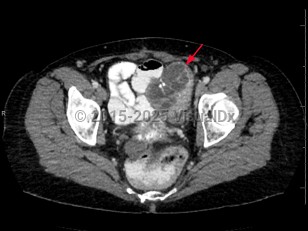

Imaging Studies image of Ovarian cancer - imageId=6846725. Click to open in gallery.  caption: '<span>Axial CT image demonstrates a  large, heterogeneous, partially solid, and cystic mass involving the left  adnexa. Biopsy results were consistent with ovarian carcinoma.</span>'

Axial CT image demonstrates a large, heterogeneous, partially solid, and cystic mass involving the left adnexa. Biopsy results were consistent with ovarian carcinoma.